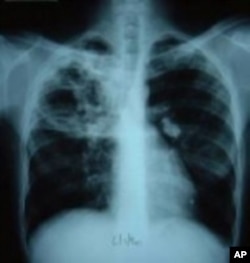

Wata mace mai suna Pinky Molefe, tana karbar maganin tarin fuka ko TB a wani asibitin unguwar Alexandria a Johannesburg, Afirka ta Kudu ranar 13 Oktoba, 2010

Wata kwayar halittar cuta wadda ke kama huhu, ita ce take haddasa tarin fuka ko TB. Idan har aka kama da wuri, ana iya warkar da wannan cuta da kwayoyin kashe cuta. Haka kuma ana iya yin rigakafinta da allurar rigakafi. Amma duk da haka, miliyoyin mutane su na kamuwa da tarin fuka su na kuma mutuwa a kowace shekara, akasari a kasashen Afirka da Asiya.